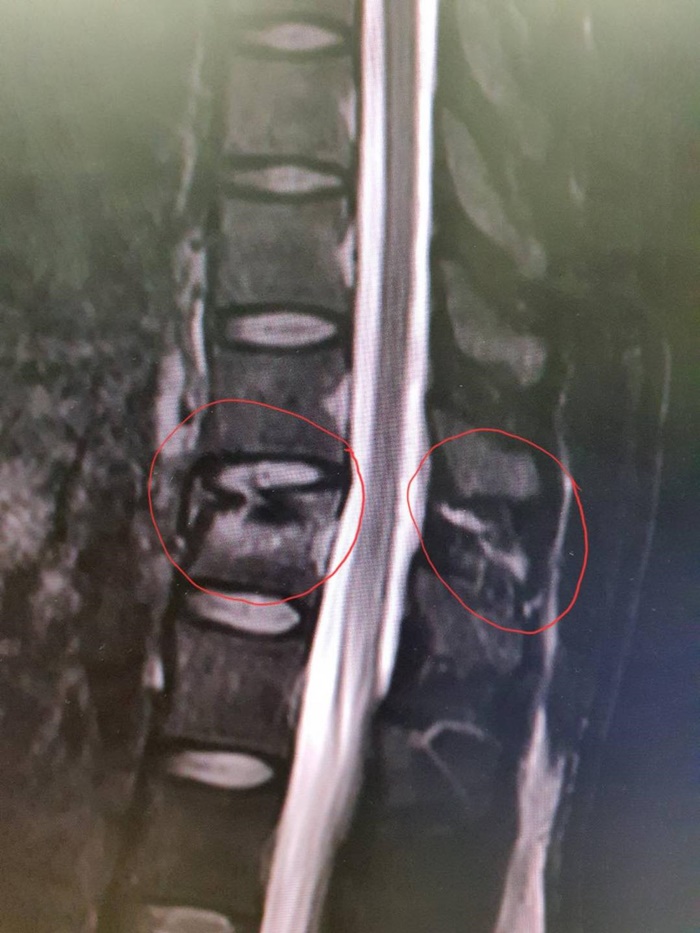

จนหล่นจากที่สูงและกระดูกสันหลังหัก และต้องทำการผ่าตัด นั้น